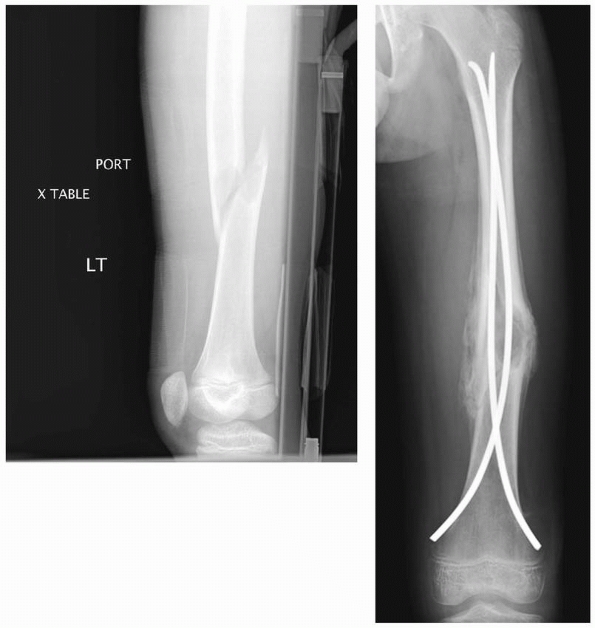

![]() |

FIGURE 22-15 A.

A few years after titanium lasting nailing, the nails have migrated proximally with growth, creating a stress riser and the subsequent insufficiency fracture. B. The refracture was treated with removal of the old nails and replacement with longer implants. |

FIGURE 22-21 A.

This proximal spiral femur fracture was deemed length-unstable and a poor candidate for titanium elastic nails. The surgeon chose an external fixator, rather than a plate. B. Eight weeks after injury, the fracture is healing in excellent alignment and there is good early callus. Fixator removal is easier than plate removal. |